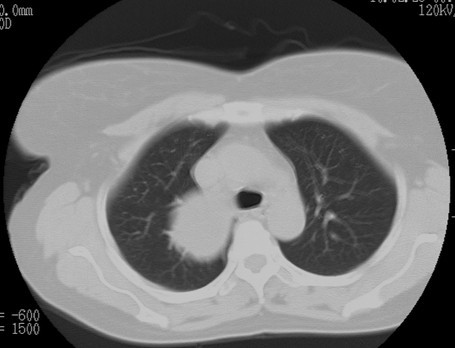

以下是引用随光逐影在2010-3-1 8:36:00的发言:[br]右上纵隔囊性占位性病变,考虑支气管囊肿,不排除神经源性肿瘤。